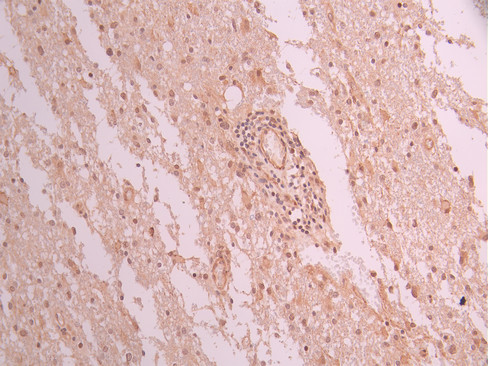

IHC image of CSB-RA546965A0HU diluted at 1:100 and staining in paraffin-embedded human glioma cancer performed on a Leica BondTM system. After dewaxing and hydration, antigen retrieval was mediated by high pressure in a citrate buffer (pH 6.0). Section was blocked with 10% normal goat serum 30min at RT. Then primary antibody (1% BSA) was incubated at 4°C overnight. The primary is detected by a Goat anti-rabbit polymer IgG labeled by HRP and visualized using 0.05% DAB.